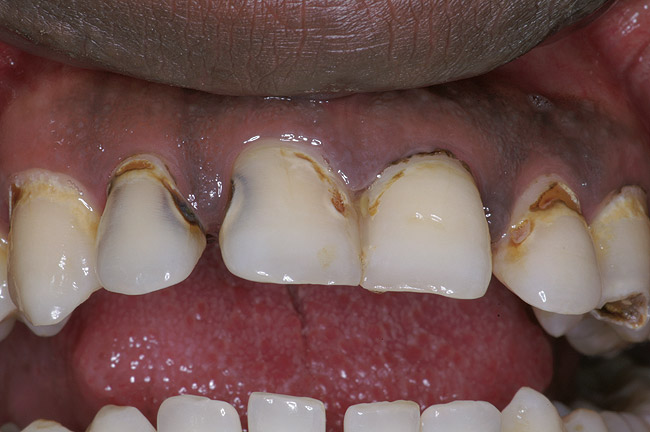

Replacement of existing restorations is responsible for 75% of all operative dentistry.15,19 The reasons for placement and replacement of restorations of direct restorative materials include: primary caries (Figure 1 and Figure 2); recurrent caries (Figure 3); poor margins (Figure 4 and Figure 5); restoration fracture (Figure 6 and Figure 7); tooth fracture (Figure 8); esthetics (Figure 9); non-carious tooth structure lost (attrition, abrasion, abfraction, erosion) (Figure 10); and pain/sensitivity.

Figure 9  Discolored, unesthetic Class IV composite resin on the maxillary left central incisor.

Figure 9